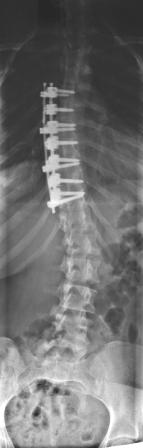

postoperative Bilder

Nur der vollständigkeit halber wollte ich noch die wirklichen postoperativen Bilder des Pat. aus dem Fernsehbeitrag zeigen. Dort wurden Bilder von einem anderen Pat. gezeigt, der präoperativ 95° hatte und viel Älter war.

Natürlich ist das optische für den Patienten wichtig, aber was für mich wichtiger ist, ist, wie sich die LWS postoperativ einstellt, ohne dass sie versteift werden muß. Wir konnten hier auf eine Lösungsop. von vorne verzichten und haben stattdessen von hinten viele kleine Osteotomien gemacht. Bei 75° präop sind 26° postop und eine gut balancierte LWS sehr erfreulich.

Man sollte diese Möglichkeit als Patient zumindest kennen, bevor man sich für oder gegen eine OP entscheidet.

- Man beachte die kurzbogige Kyphose mit den Keilwirbeln thrakolumbal und die kompensatorische Hyperlordose.

Der Pat. hatte hier häufig Schmerzen. - Kyphose_präop.jpg (8.7 KiB) 22717 mal betrachtet

- Durch die Ausgradung der BWS stellt sich die LWS automatisch physiologischer ein.

- Kyphose_postop.jpg (8.95 KiB) 22717 mal betrachtet